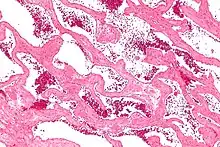

| Micrograph of a cavernous liver hemangioma. H&E stain. | |

Liver cavernous hemangioma

Cavernous hemangiomas are erroneously called the most common benign tumors of the liver.[13] Usually one malformation exists, but multiple lesions can occur in the left or right lobe of the liver in 40% of patients.[3] Their sizes can range from a few millimeters to 20 centimetres. Those over 5 cm are often referred to as giant hemangiomas.[3] These lesions are better classified as venous malformations.